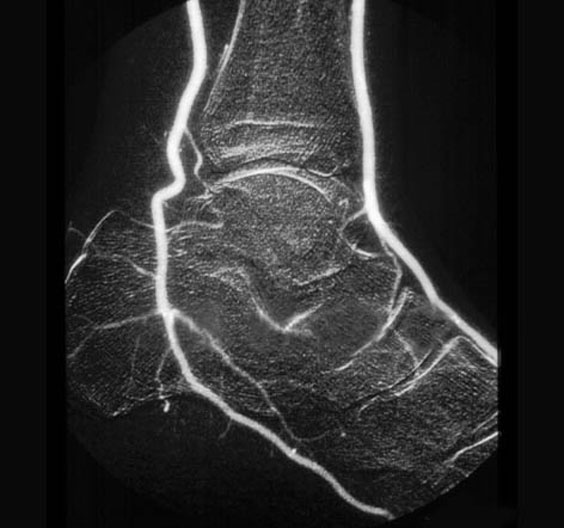

Foot Arteriogram

1. Posterior tibial artery

2. Calcaneous

3. Navicular bone

4. Anterior tibial artery

5. Tibia

6. Talus

7. Dorsalis pedis

8. Cuneiform